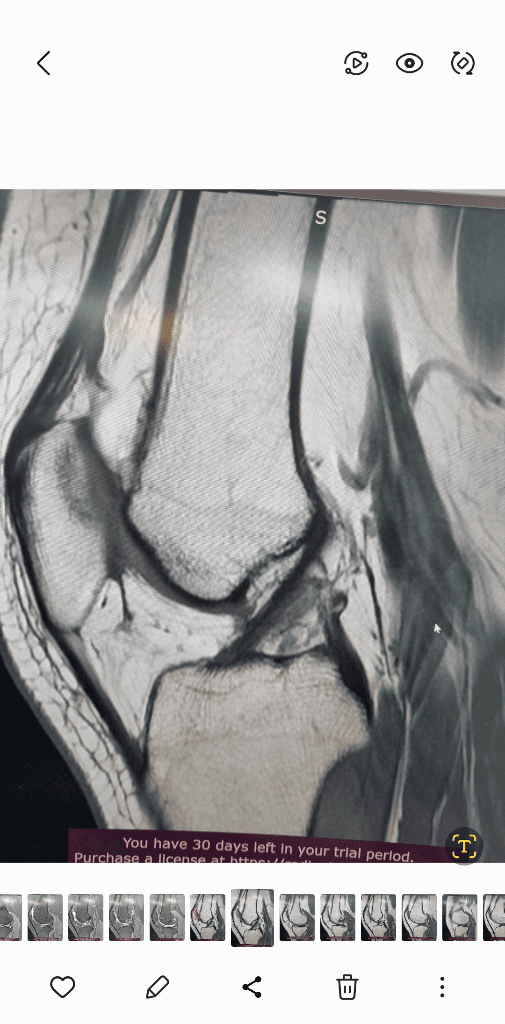

MRI는 신호가 다른 다른 사진들이 있을겁니다.

그런걸 종합적으로 판단해야 정확히 알수 있습니다.

검사한 병원에 판독요청하세요.